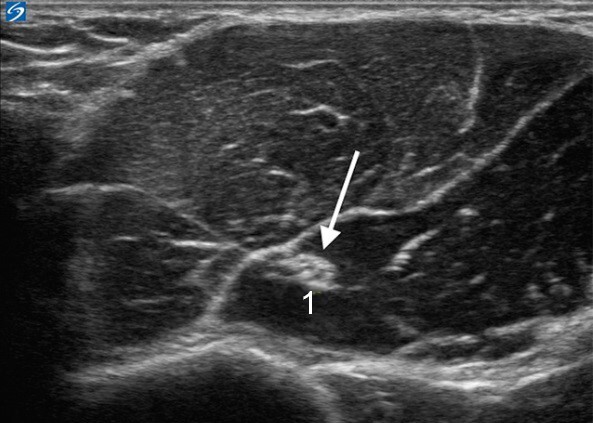

肌皮神经图像

肌皮神经